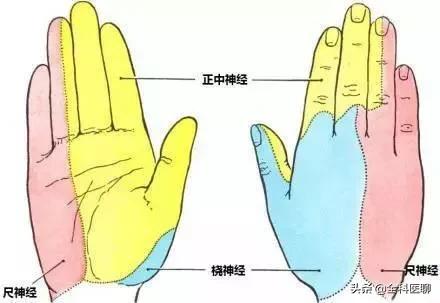

指の知覚神経は頸髄から神経根に分かれ、頸部腋窩で腕神経叢を形成し、上腕と前腕を通って橈骨神経、正中神経、尺骨神経となり、手と指に分布する末梢神経となる。

尺骨神経の損傷。同じ側の小指と薬指のしびれや痛み、一部の指の運動障害を引き起こすことがある。肘の後方にある尺骨神経の溝は、損傷や圧迫を受けやすい。

正中神経損傷: 前腕と上腕の正中神経は、外傷、腫瘍、圧迫などにより、手掌面、親指、人差し指、中指にしびれや痛みを生じる。手首は、手根管症候群と呼ばれる損傷や圧迫に対して最も脆弱であり、治療原則は以前と同じです。

橈骨神経の損傷橈骨神経は上腕側面の中央から下部にかけて傷害を受けやすく、親指と人差し指の甲のしびれや痛み、指と手首の下垂を伴う。

頚髄神経根を分割し、頸部に形成する。腕神経叢分ける橈骨神経、正中神経、尺骨神経経絡は上腕と前腕を等距離に通過し、最終的に頚椎となる。末梢神経手と指に分布している。そのため、指先のしびれは必ず上記の神経に問題がある。

2.橈骨神経、正中神経、尺骨神経の損傷

上腕外側面の中央下部にある橈骨神経は、次のような影響を受ける。圧迫、外傷、腫瘍などにつながる可能性がある。親指と人差し指の裏側のしびれと痛み、指と手首の下垂。.正中神経が損傷すると、次のようなことが起こる。手のひら、親指、人差し指、中指のしびれと痛み。尺骨神経の損傷はその結果である。尺骨神経の損傷は、その後、次のような結果をもたらす。同側の小指と薬指にしびれと痛みがあり、一部の指の動きが悪くなる。

手の指はさまざまな神経に支配されている。

親指、人差し指、中指の半分は正中神経に支配されている。

小指、薬指、中指の残り半分は尺骨神経に支配されている。